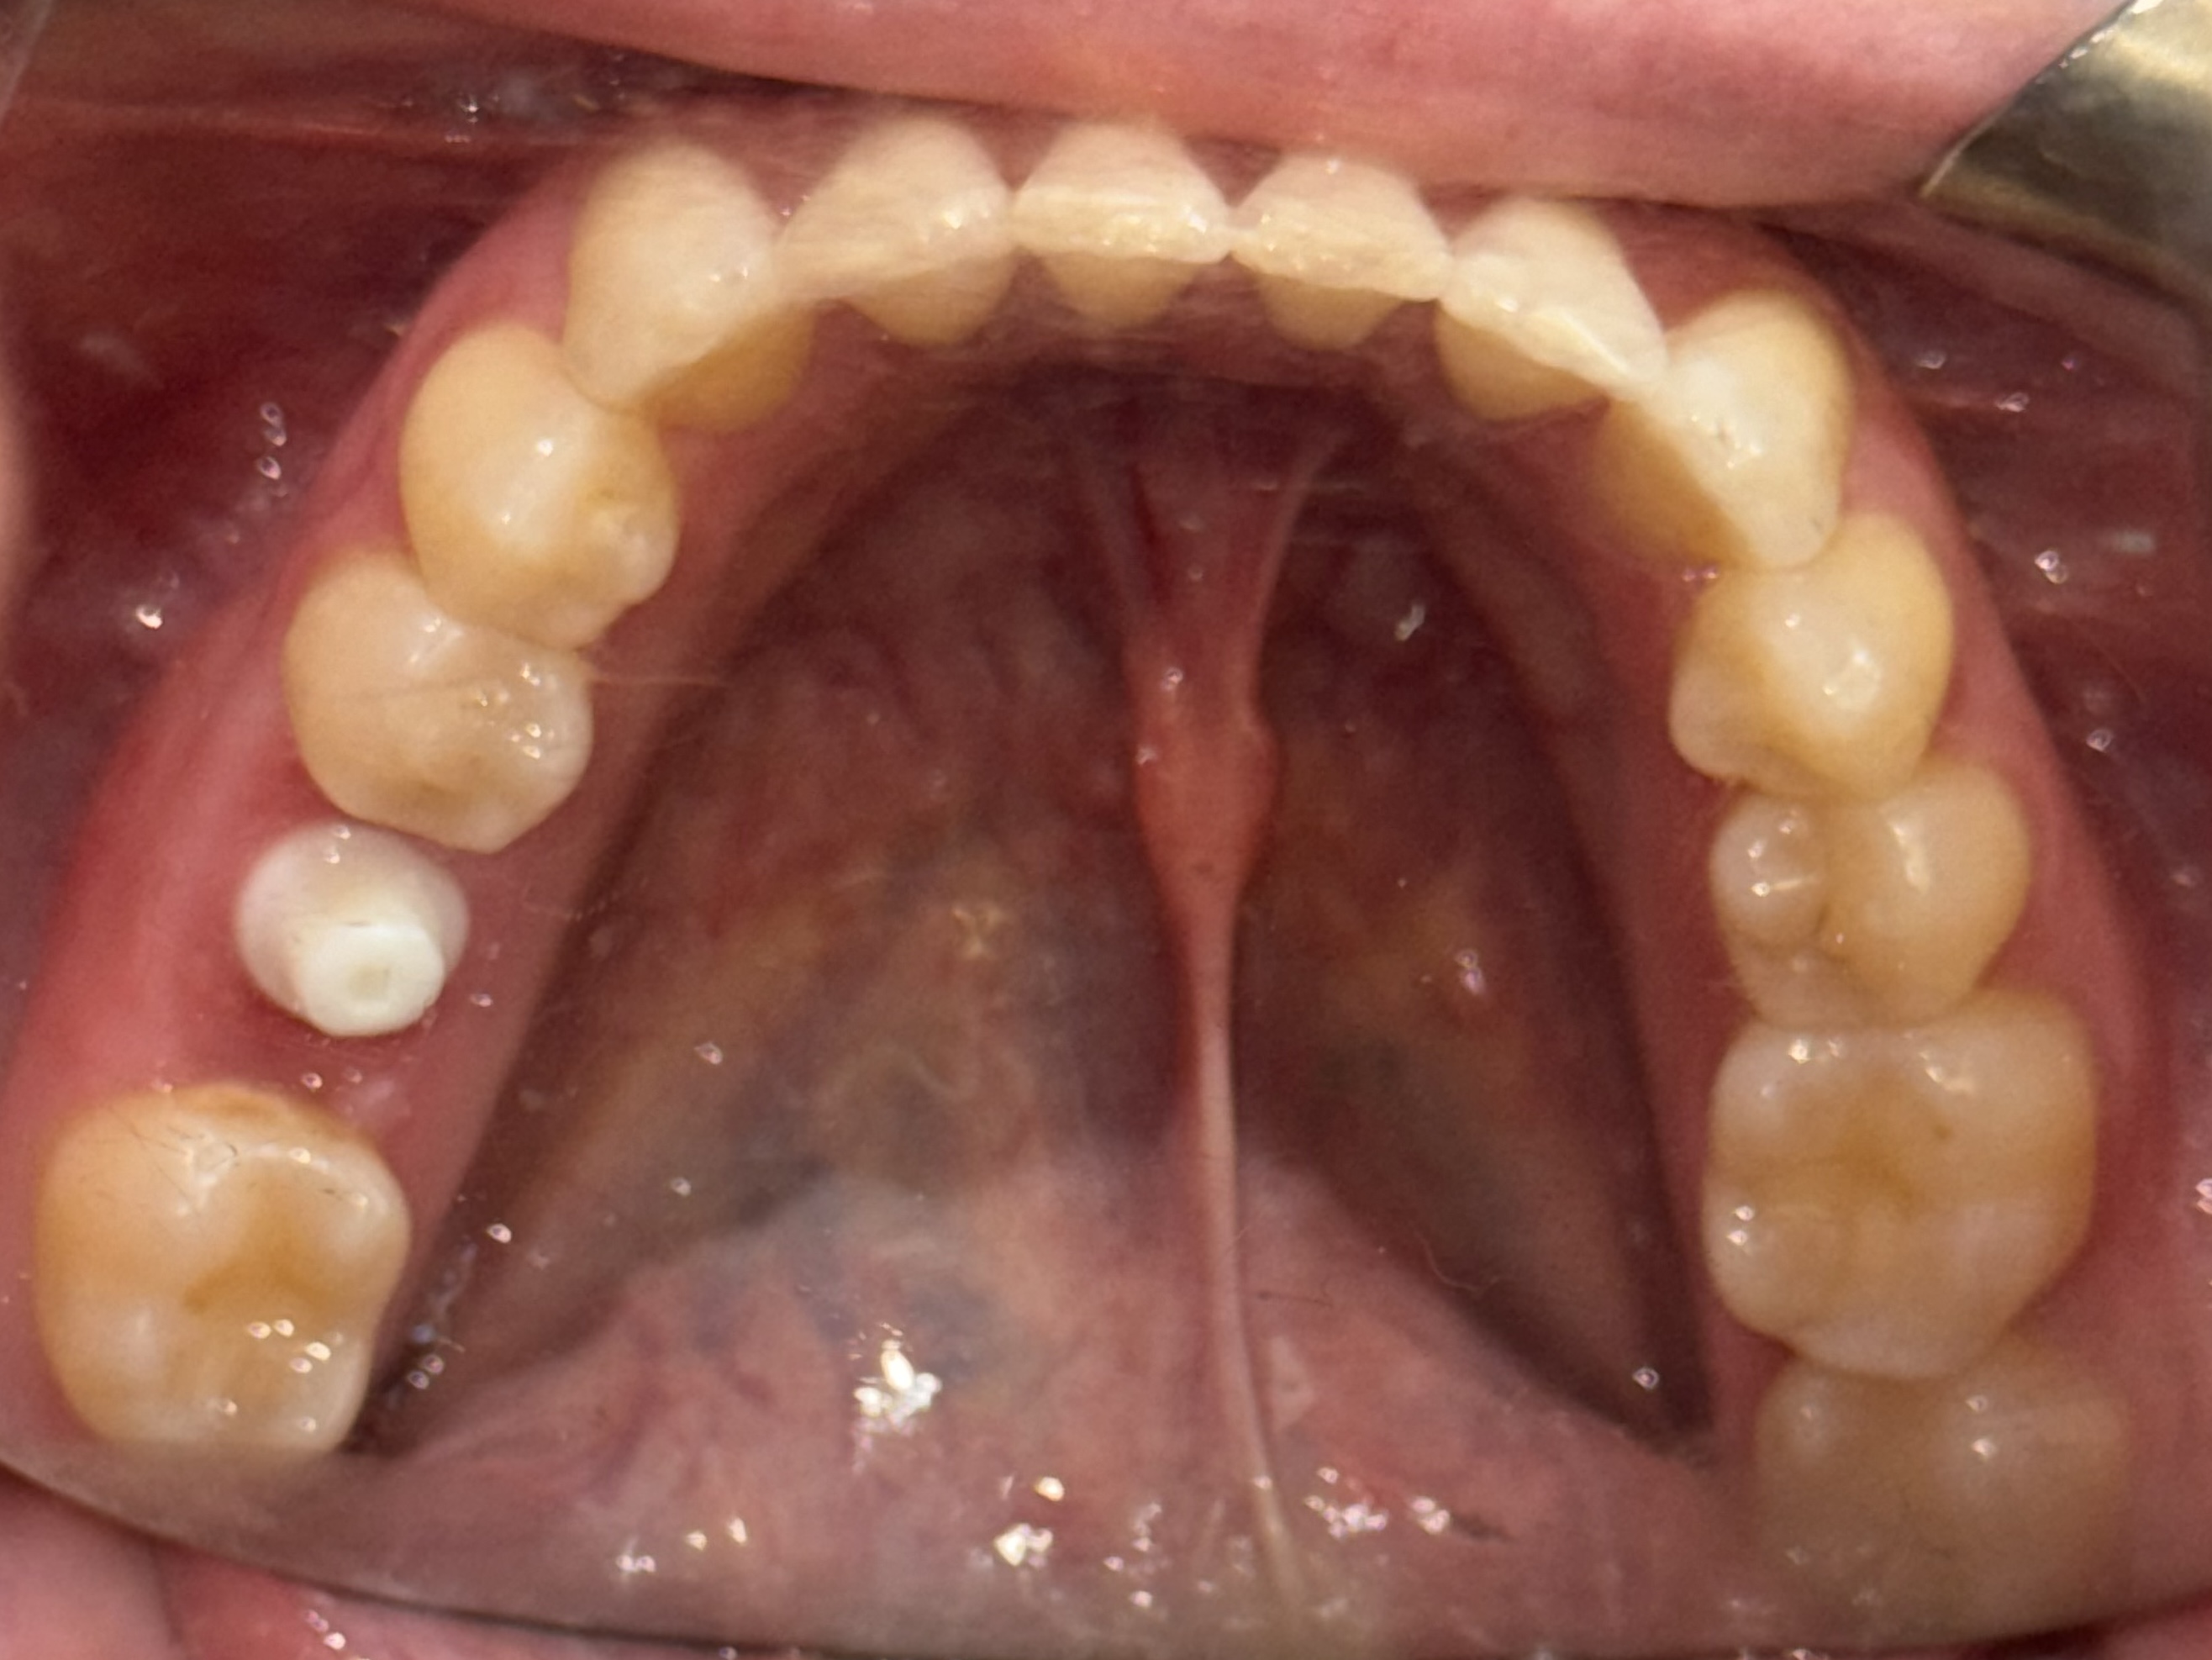

Comprehensive biological oral surgery case showing Tooth #30 extraction, guided bone regeneration, implant placement, and crown restoration using Groton Wellness’ minimally invasive, biologically supportive protocols.

This case follows Jennifer, a 47-year-old female, through the full biological treatment sequence: from extraction of Tooth #30 to guided bone regeneration, implant placement, and final crown restoration. Each step was planned with CBCT-based visualization and executed using open wound healing principles to support long-term oral and systemic wellness.

Visual Case Progression

All clinical images are shown at a consistent size for easy comparison.